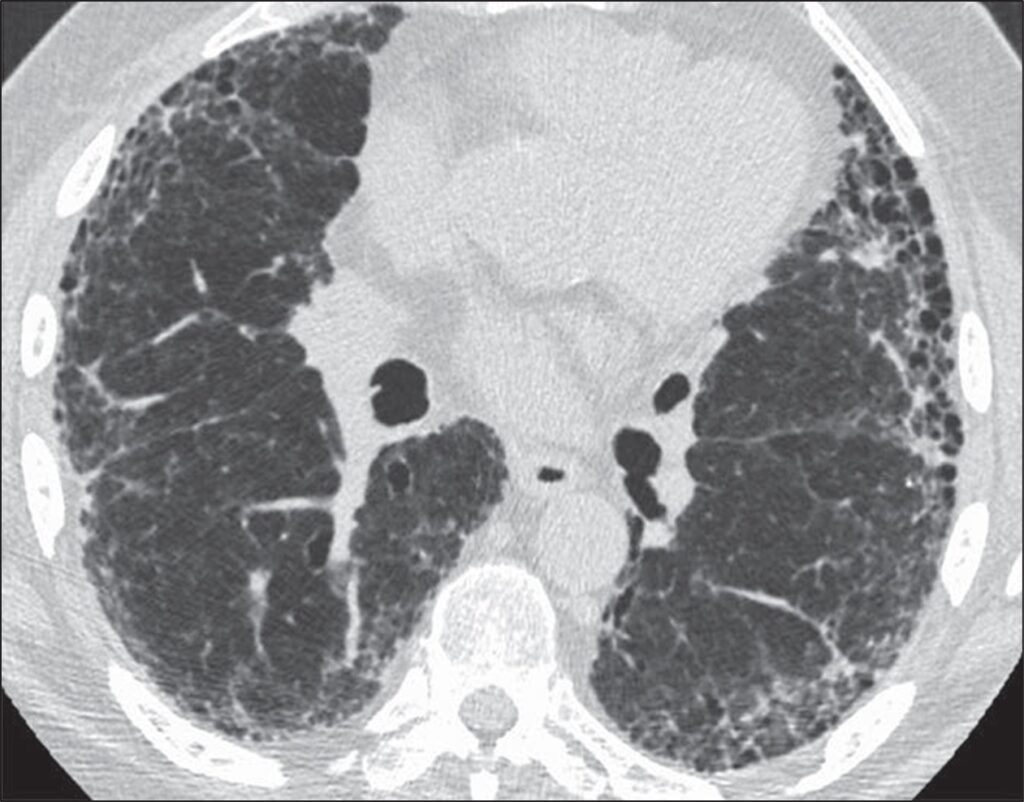

The goals of the radiologist in the evaluation of a patient with suspected pulmonary fibrosis are to determine whether a diffuse lung disease is present, determine the pattern of fibrosis, and provide an appropriate differential diagnosis. Usual interstitial pneumonia (UIP) pattern of pulmonary fibrosis is the most common ILD. UIP is most frequently idiopathic, but can also be secondary to connective tissue disease, medications, or exposure to asbestos [2]. Given the pervasiveness of this diagnosis, radiologists participating in the multidisciplinary diagnosis of patients with suspected ILD are frequently asked whether CT findings support a UIP diagnosis.Fortunately, guidelines can increase the confidence of radiologists in correctly identifying patients with UIP. The American Thoracic Society guidelines for the diagnosis of UIP pattern break down CT findings into four categories: UIP, probable UIP, indeterminate for UIP, and alternative diagnosis. The CT findings indicative of UIP pattern include subpleural and basal predominant fibrosis in addition to honeycombing, with or without traction bronchiectasis (Fig. 1).

Fig. 1—73-year-old man with idiopathic pulmonary fibrosis. HRCT scan shows usual interstitial pneumonia pattern of fibrosis characterized by subpleural and basal distribution of fibrosis with honeycombing.